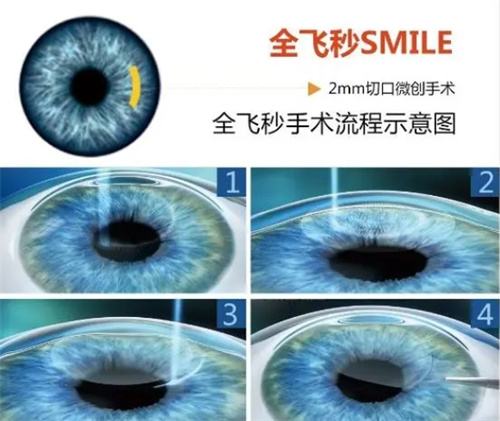

3. 飞秒辅助ICL(智臻飞秒ICL)

飞秒ICL(基础版):3.36万~3.7万元/双眼(郑州爱尔眼科3.36万元起)

飞秒TICL(散光版):3.76万~4.1万元/双眼(郑州爱尔眼科3.76万元起)

适用人群:

追求更高精密度的患者

近视超1800度且散光显著者

手术方式:飞秒辅助ICL比传统ICL贵6000~8000元。